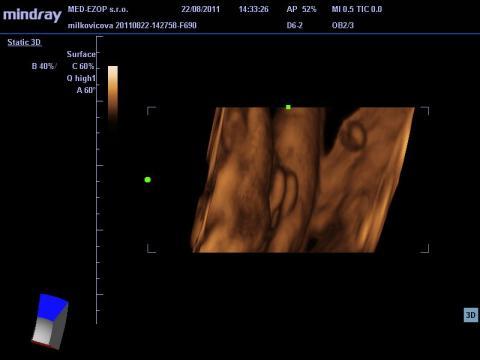

Dobrý deň, poprosím o váš názor, nakoľko som dosť napätá, vzhľadom na tlak okolia, manžela, ktorý túži po vyhranenom pohlaví. Raz mi hovoria na UZ, že to bude chlapec, raz dievča. Naposledy som bola v 34tt. Prikladám foto. Aký je váš názor? Dá sa to jednoznačne potvrdiť? Ďakujem

Pokiaľ ani lekári nie sú si na 100% istí, tak s tým nič nenarobíte a dozviete sa to až po pôrode. Ja si osobne myslím, podľa fotky, ktorú ste poskytla, že to vypadá skôr na dievčatko.

No dle mého názoru to vypadá na chlapečka, 2 varlátka a směrem dolu pinďourek. No nevím ale přeju vám to.

Ale toto je myslím foto odzadu, kolienka hore...prečo je tam tá ryha medzi?

ja som to videla rovnako ako máte Vy na foto, podľa mňa je to dievčatko, aj moja dcéra to tak mala.

Takže dávam na vedomie, že sa narodilo zdravé dievčatko